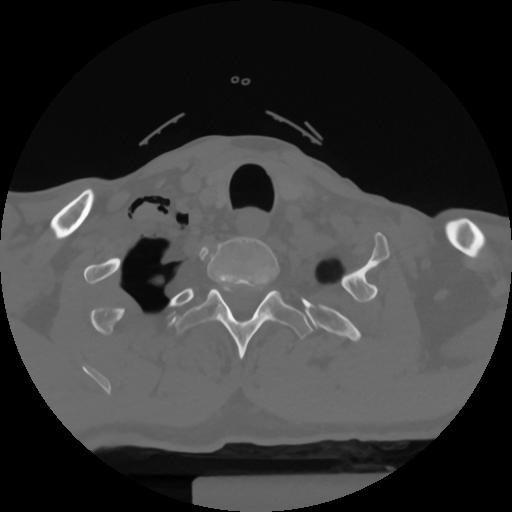

12 P.BLANDAS,,Vol,0.5,P.BLANDAS,,